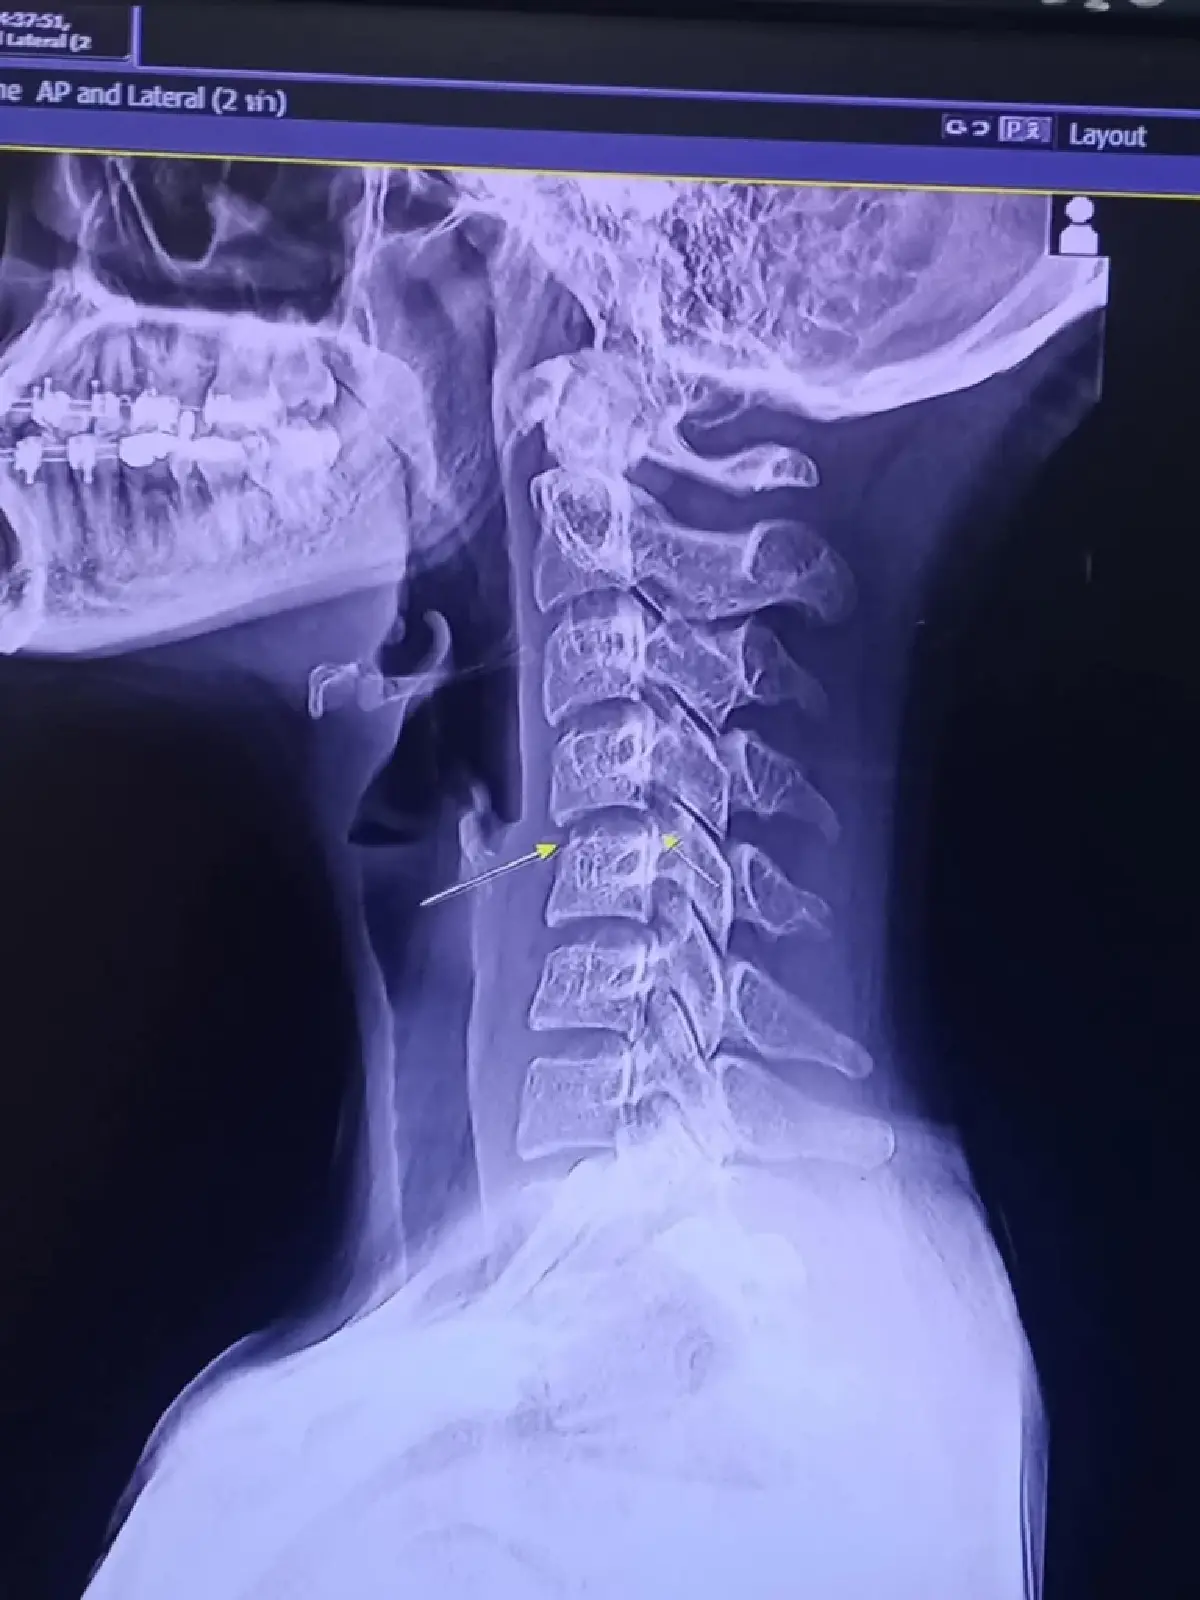

โดย นพ.สุรัตน์ ตันประเวศ แพทย์ผู้เชี่ยวชาญ โรคระบบประสาทและสมอง ได้โพสต์เฟซบุ๊ก ระบุว่า สาเหตุการเสียชีวิตอาจจะไม่ใช่จากการนวดนะ แต่น่าจะมีอักเสบและติดเชื้อ เนื่องจาก “x ray ไม่พบมีกระดูกกดสันหลัง”

และยังระบุอีกว่า " คนไข้ ที่เสียชีวิต อาจไม่ใช่จากการนวดนะครับ เห็นว่า น่าจะมีอักเสบและติดเชื้อ x ray ไม่พบมีกระดูกกดสันหลัง

2. จาก x ray กระดูกโดนกด ผิดรูปจริง แสดงว่า โดนกดหรือบิดแรงมากๆๆ แต่ ไม่รู้เป็นเหตุจนกดไขสันหลังไหม